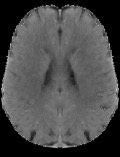

Accurate infarct segmentation in non-contrast CT (NCCT) images is a crucial step toward computer-aided acute ischemic stroke (AIS) assessment. In clinical practice, bilateral symmetric comparison of brain hemispheres is usually used to locate pathological abnormalities. Recent research has explored asymmetries to assist with AIS segmentation. However, most previous symmetry-based work mixed different types of asymmetries when evaluating their contribution to AIS. In this paper, we propose a novel Asymmetry Disentanglement Network (ADN) to automatically separate pathological asymmetries and intrinsic anatomical asymmetries in NCCTs for more effective and interpretable AIS segmentation. ADN first performs asymmetry disentanglement based on input NCCTs, which produces different types of 3D asymmetry maps. Then a synthetic, intrinsic-asymmetry-compensated and pathology-asymmetry-salient NCCT volume is generated and later used as input to a segmentation network. The training of ADN incorporates domain knowledge and adopts a tissue-type aware regularization loss function to encourage clinically-meaningful pathological asymmetry extraction. Coupled with an unsupervised 3D transformation network, ADN achieves state-of-the-art AIS segmentation performance on a public NCCT dataset. In addition to the superior performance, we believe the learned clinically-interpretable asymmetry maps can also provide insights towards a better understanding of AIS assessment. Our code is available at https://github.com/nihaomiao/MICCAI22_ADN.